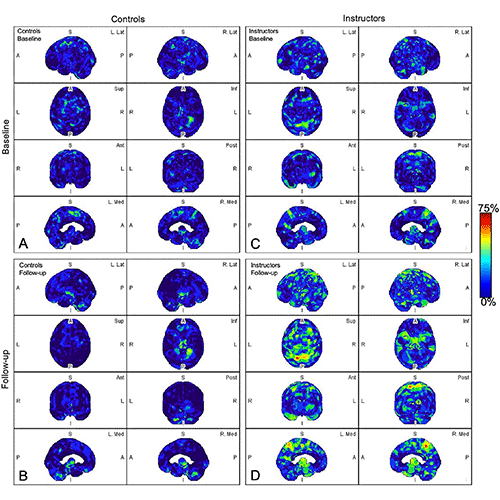

Parametric maps of amyloid deposition in healthy control participants (A and B) and blast-exposed military instructors (C and D) at baseline (A and C) and follow-up (B and D). The blue-to-red scale indicates the frequency of statistically abnormal amyloid uptake in a particular brain voxel. Whereas no abnormal amyloid uptake was identified at baseline or follow-up in healthy control participants (A, B), amyloid deposition occurred most frequently in blast-exposed participants in the superior parietal lobules, precuneus, cingulum, paracentral lobules, and anterior temporal and occipital lobes (D). A = anterior, Ant = anterior, I = inferior, Inf = inferior, L = left, Lat = lateral, Med = medial, P = posterior, Post = posterior, R = right, S = superior, Sup = superior.

Abnormal amyloid accumulation was seen in six of the nine participants who were exposed to explosions. Three of the participants had one region of the brain with increased amyloid accumulation, two participants had two regions, and one participant had three regions with abnormal accumulation.

None of the healthy control participants showed any abnormal amyloid accumulation.